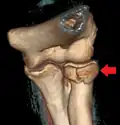

| Radial head fracture (red arrow) with posterior and anterior sail sign (blue arrows) | |

Radial head fractures are diagnosed from a clinical assessment and diagnostic imaging.[7] Symptoms may include pain or tenderness at the radial head, bruising, swelling, and a limited range of motion of the injured elbow.[2] Diagnostic imaging may include ultrasound, plain radiography (x-ray imaging), Computed tomography scan (CT), and magnetic resonance imaging (MRI).[2][4] A fat pad sign may be present on diagnostic imaging and may indicate a radial head fracture.[5]